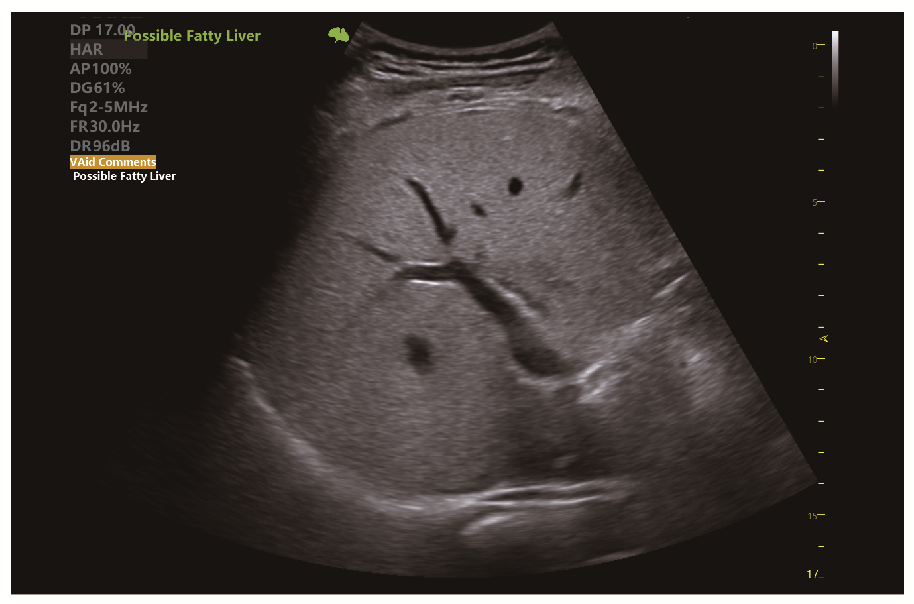

• VAid Liver автоматичне виявлення захворювань печінки

• VAid Liver - автоматичне виявлення вогнищевих і дифузних захворювань печінки з кількісним аналізом

Клінічні зображення, що демонструють якість діагностики та можливості обладнання

Клінічне зображення 3